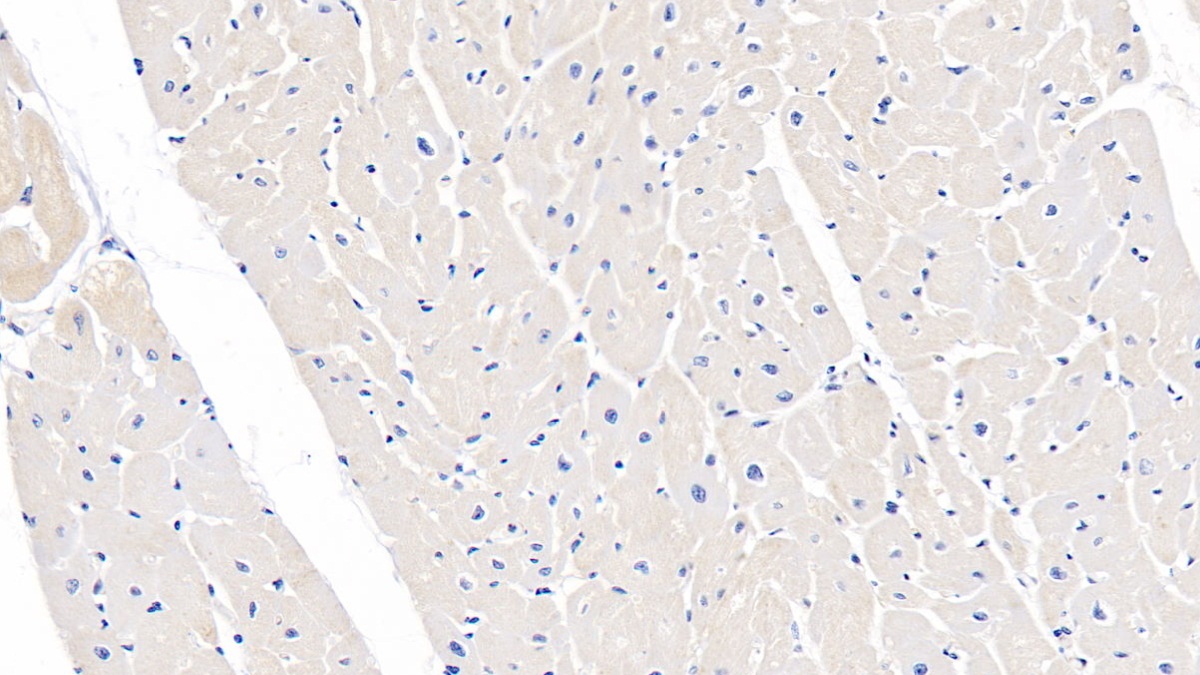

Polyclonal Antibody to Tuberous Sclerosis Protein 1 (TSC1) (PAC813Hu01)

| Название антигена | Tuberous Sclerosis Protein 1 (TSC1) |

| Валидировано для | IHC WB Иммуногистохимия; Вестерн-блоттинг |

| Рекомендуемые разведения | WB: 0.01-2 мкг/мл; IHC: 5-20 мкг/мл; ICC: 5-20 мкг/мл; Оптимальное разведение определяется конечным потребителем |